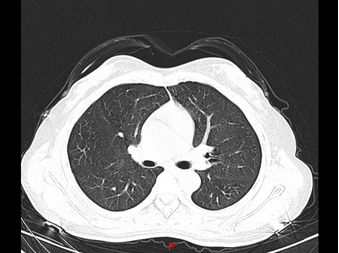

正当大家毫无头绪之时,该院呼吸与危重症医学科主任发现了端倪。原来,两位女士居家期间,因为害怕感染新冠肺炎,每天定时在家喷洒高浓度84消毒液,又没有开窗通风,从而引起过敏性肺泡炎。所幸,经过3天的抗过敏治疗后,二人复查胸部CT,影像基本恢复正常。

过敏性肺泡炎治疗前与治疗后CT影像